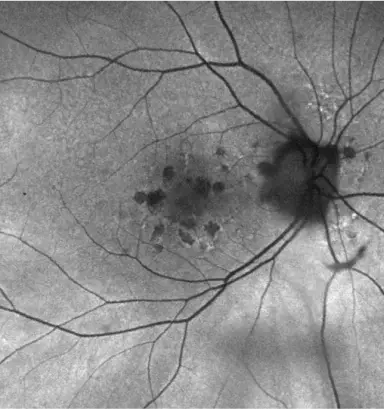

IZERVAY™ (avacincaptad pegol intravitreal solution) is indicated for the treatment of geographic atrophy (GA) secondary to age-related macular degeneration (AMD)